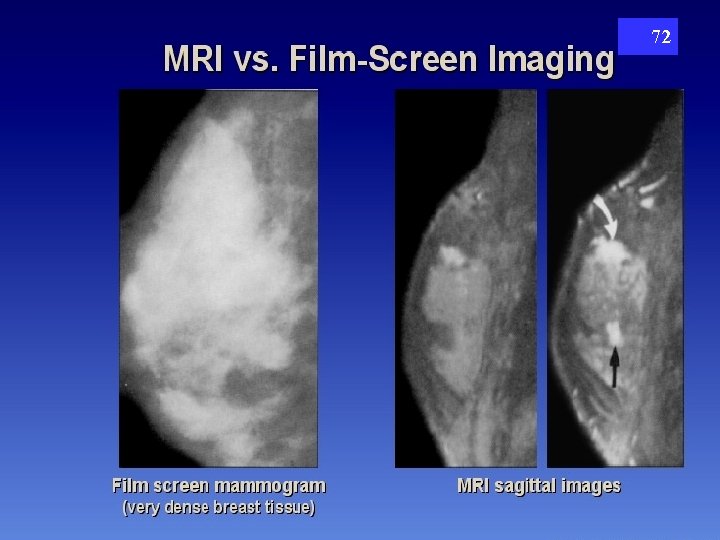

72